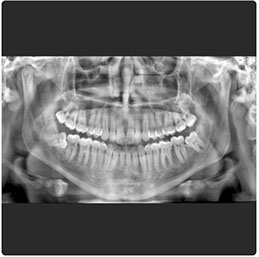

Eagle 2D Pan/Tele

El Eagle 2D Pan/Tele ofrece todos los exámenes en el perfil panorámico (panorámica estándar, senos maxilares, baja dosis, bitewing, ATM, ortogonalidad perfeccionada, panorámica infantil y bitewing ortogonalidad perfeccionada) y todos los exámenes en el perfil cefalométrico (Posteroanterior, Antero-posterior, 45 Grados, Lateral, Carpal, PA de Walters, Axial Bazal, Hirtz).

Radiografía Panorámica Digital

Radiografía Panorámica